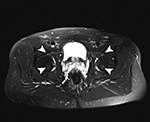

This common MR artifact, also known as aliasing, occurs when imaging with a too small field of view (FOV) that is insufficient to cover the tissues being imaged. The resulting artifact appears as a superimposition of the phase encoded signal from outside and within the FOV giving resultant wraparound of structures on the opposite side of the image (Figure 17). Wraparound artifacts are always encountered in the phase-encoding direction as the MR system oversamples in the frequency encoding direction (Zhuo, 2006).

Wraparound Artifact. Axial proton-density-weighted MR image of the right knee demonstrates wraparound artifact (arrow) of the left knee, which is partially imaged (arrowhead).